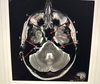

A points to A. 3rd ventricle B. Basal ganglia C. Anterior horn lateral ventricle D. Posterior horn lateral ventricle

B. Basal ganglia

D points to A. 3rd ventricle B. Thalamus C. Lentiform nucleus D. Caudate nucleus

Lentiform nucleus